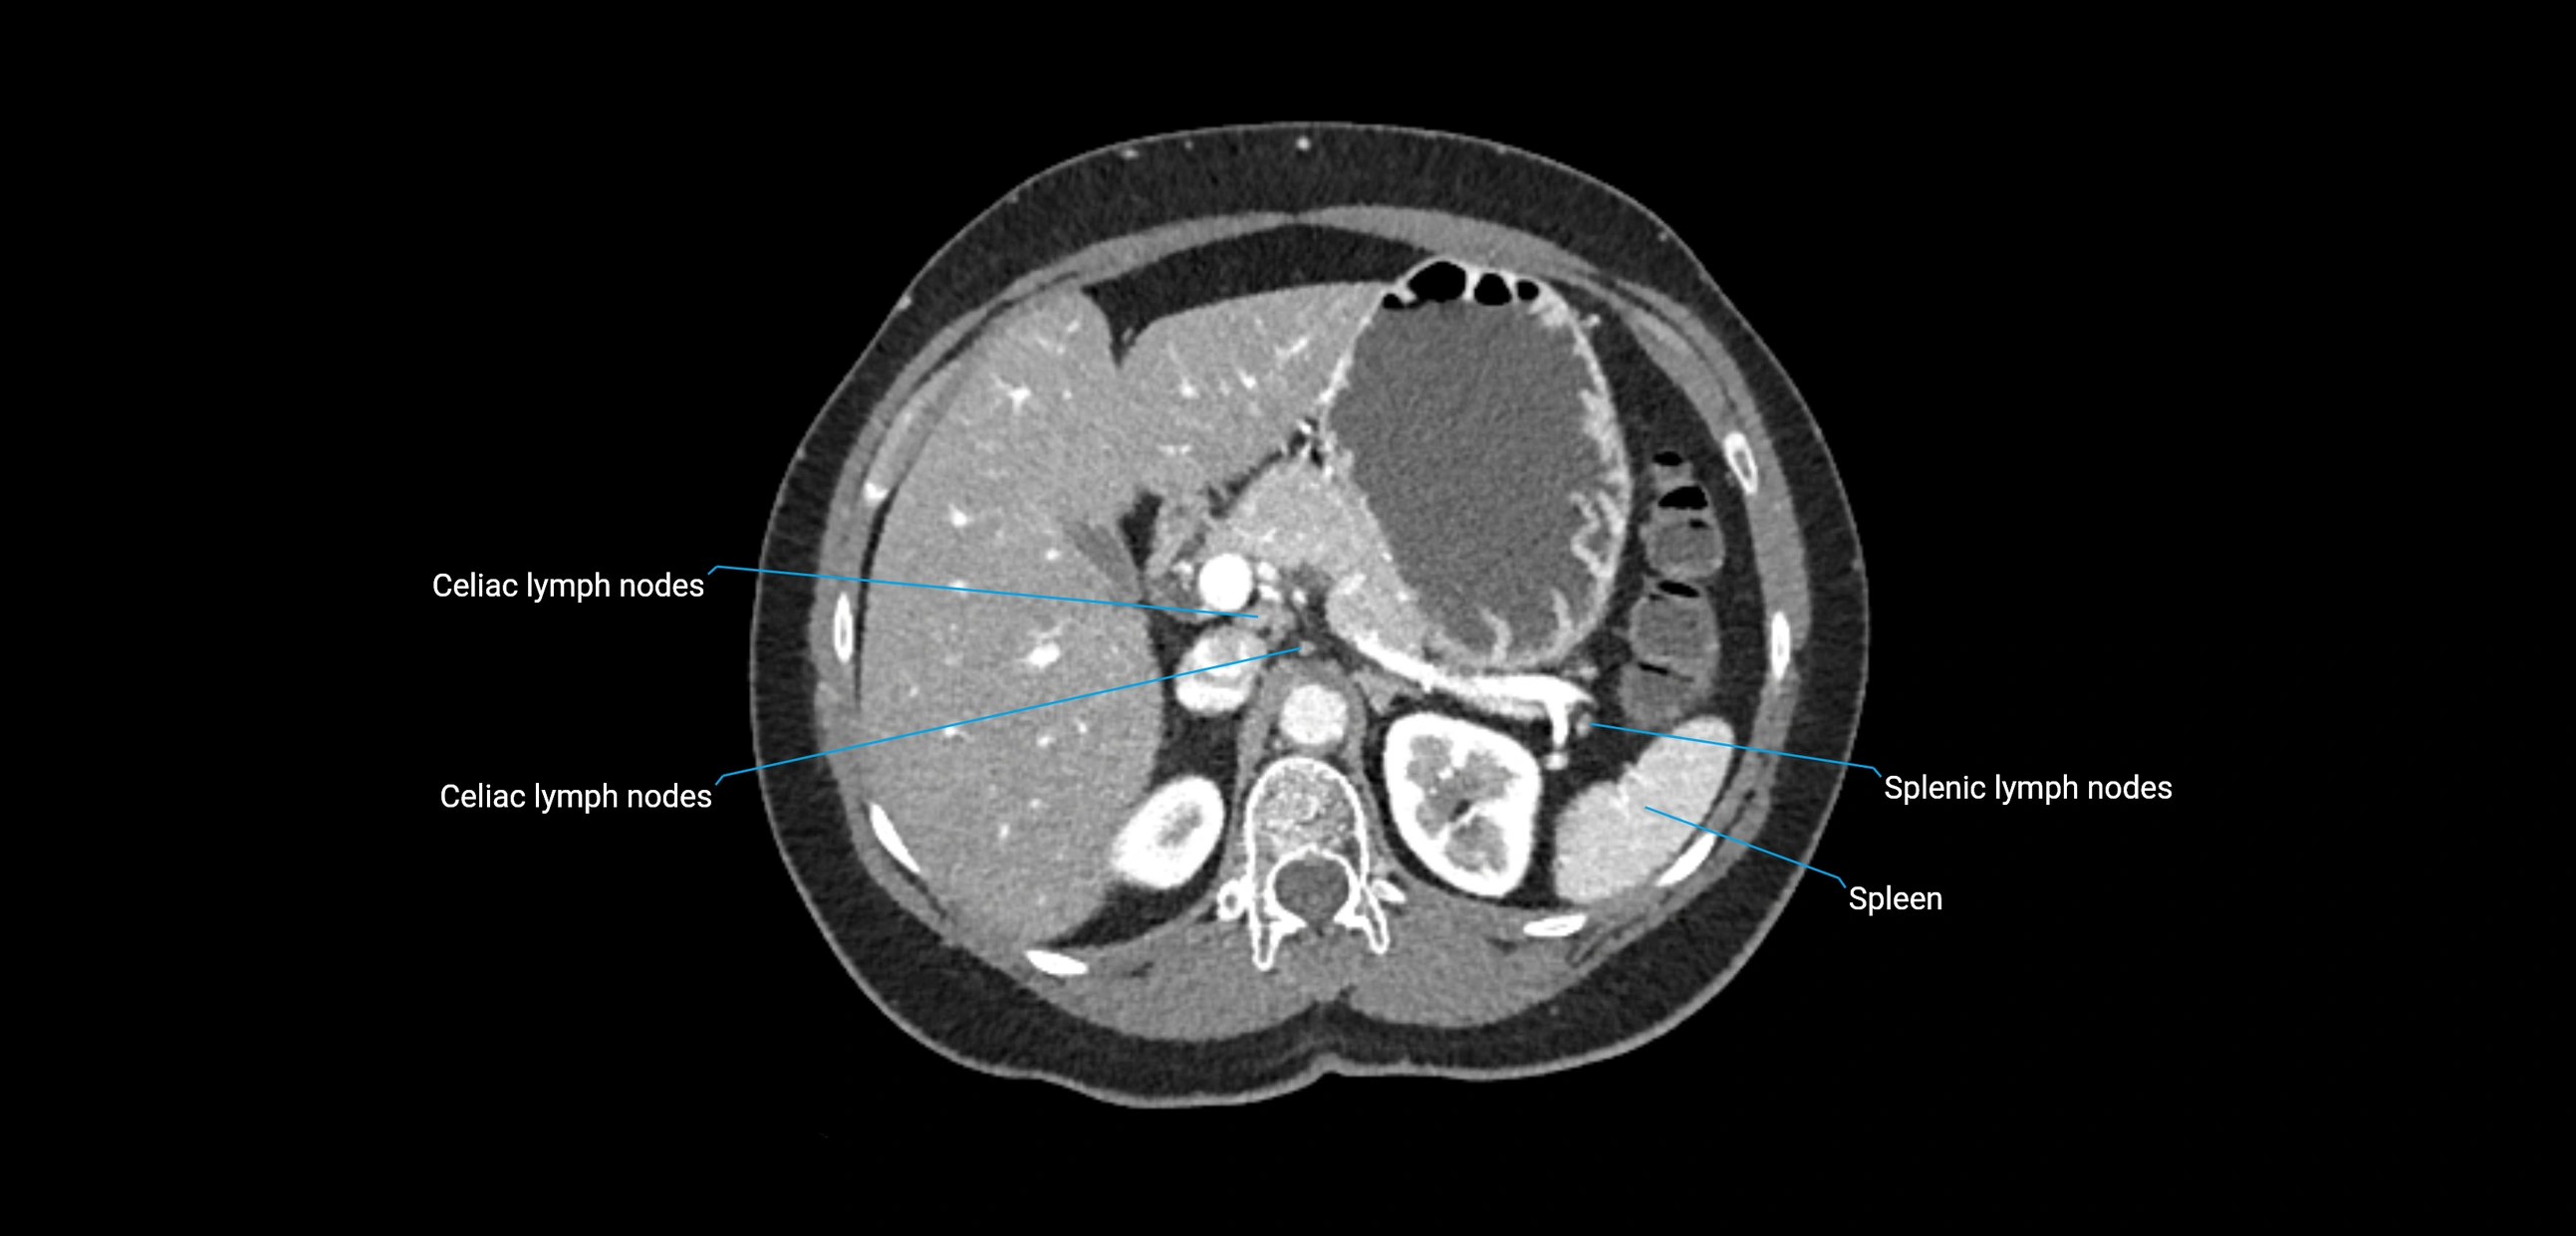

CT Appearance

CT Pre-Contrast:

• Nodes appear as soft-tissue density nodules adjacent to the aorta and IVC

CT Post-Contrast:

• Normal nodes enhance homogeneously

• Malignant nodes may show heterogeneous enhancement, central necrosis, or conglomerate formation

• Size >1 cm short axis is suspicious, though morphology and distribution are equally important